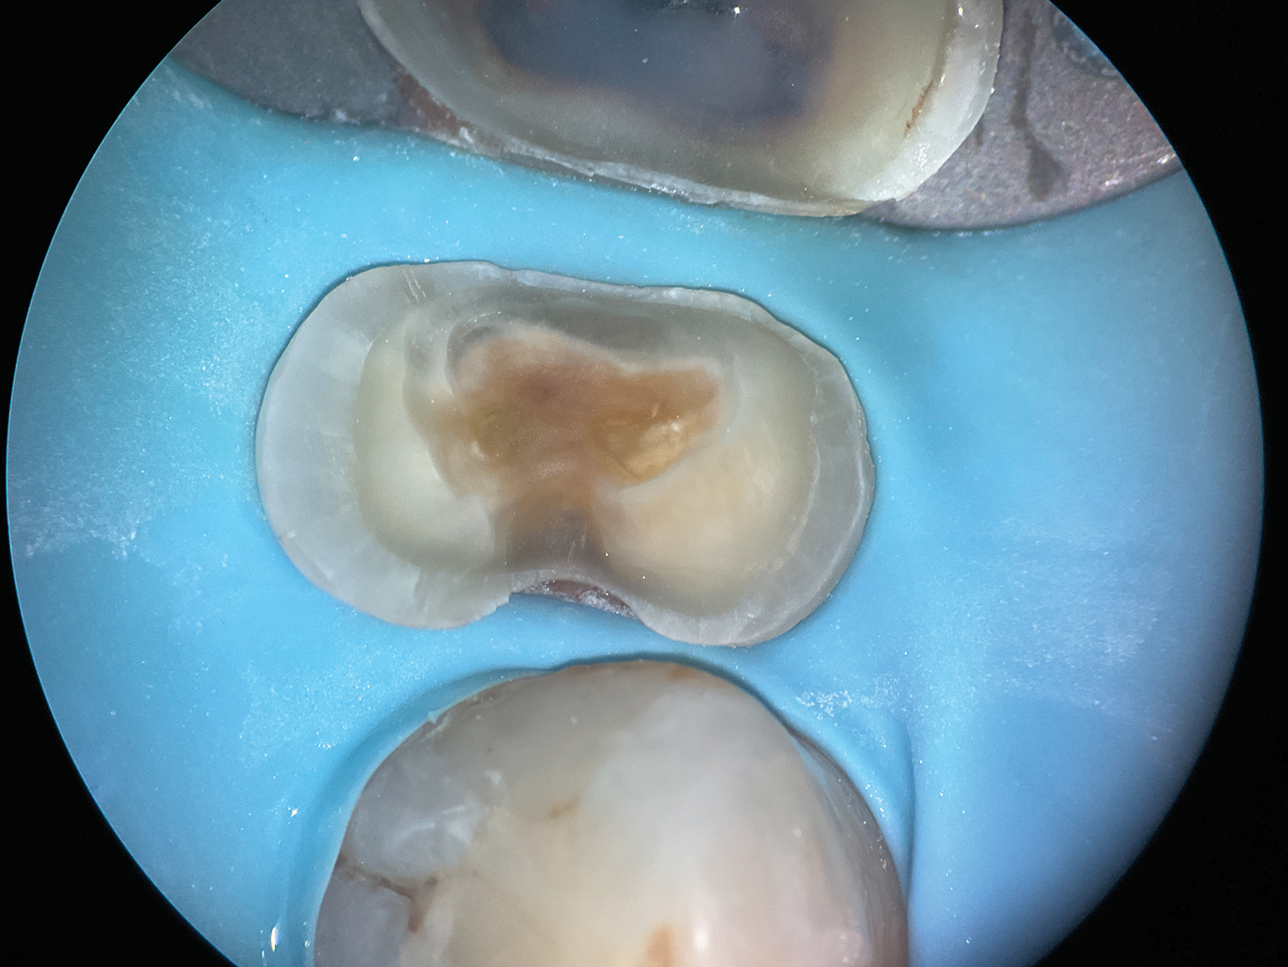

(2.) Close-up occlusal view of a maxillary first premolar during restorative treatment revealing a mesial structural crack.

Figure 2

(3.) Close-up occlusal view of the maxillary first premolar after removal of the thin cusps and dissection of the mesial crack, which resulted in a subgingival margin.

Figure 3